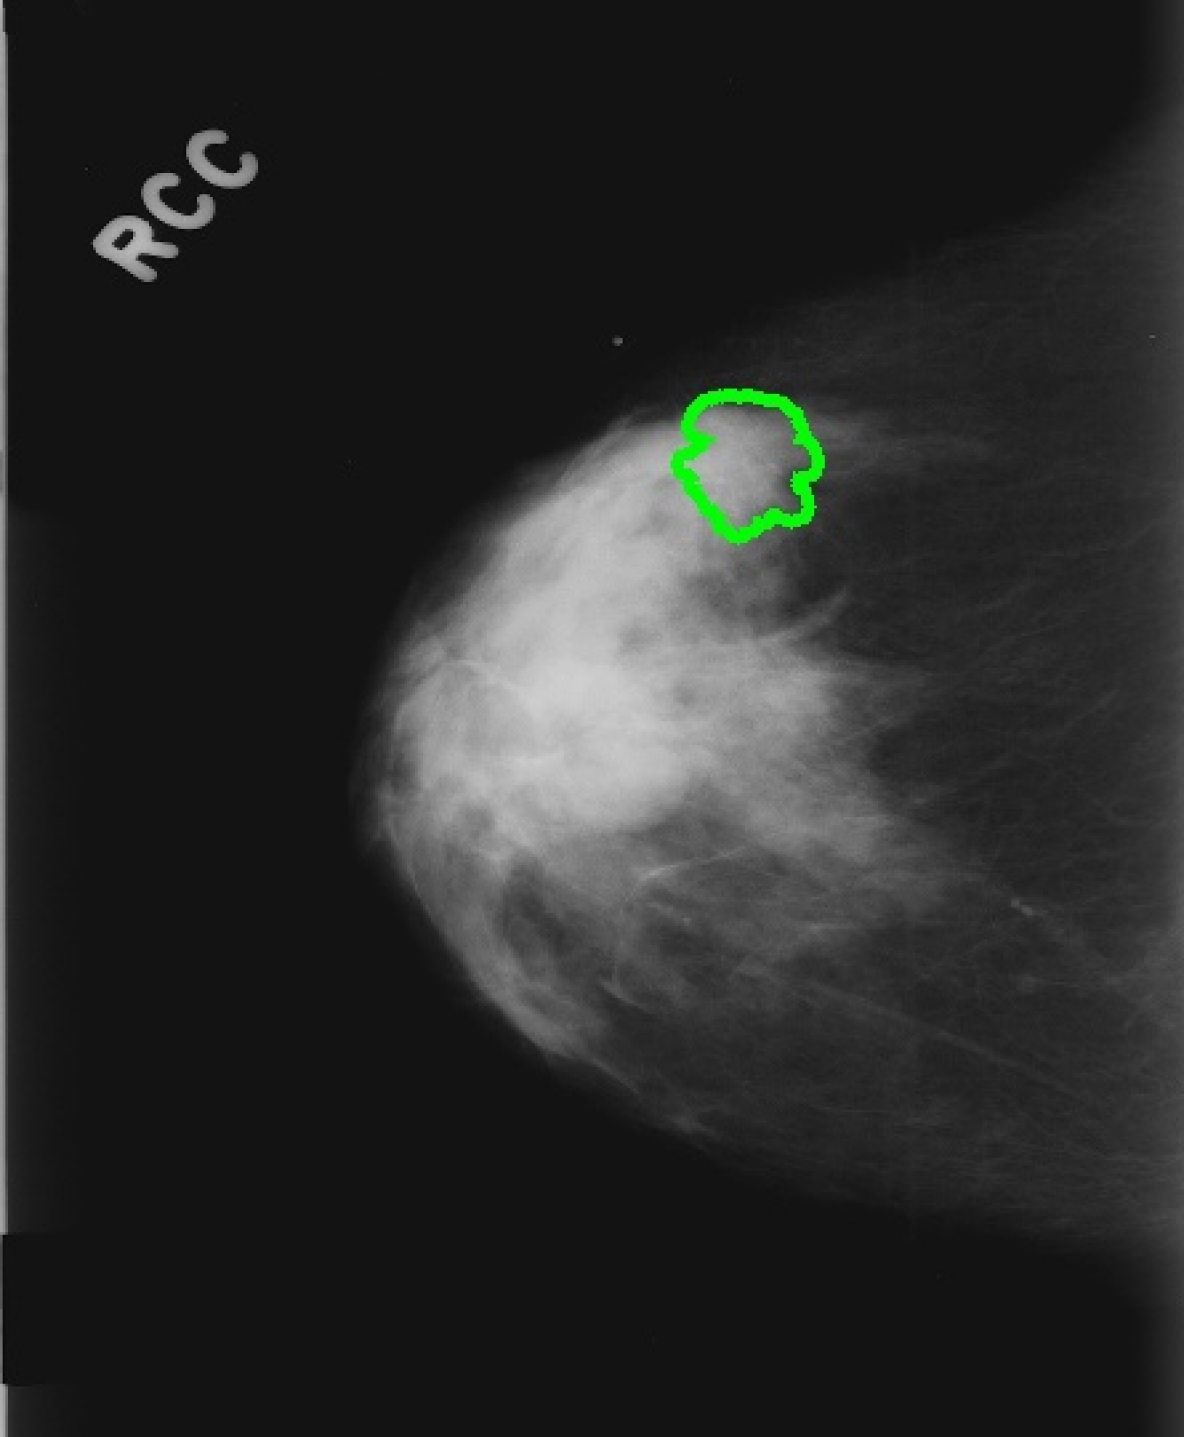

Figure 3: Result attribution heatmaps for mammography [17] and chest X-ray [14]: (a) original image overlayed with annotation contours (and arrows for missing GT), (b) our attribution framework. (c) GradCAM [25] (d) Saliency [26].

Attribution: We compared our attribution network against the gradient explanation saliency map [26] (SAL), and the network/gradient-derived GradCAM [25] visualizations. We limited our comparisons to these direct approaches, as they are widely used within medical imaging [13], and inherently valid [2]. Popular reference based approaches either utilize blurring, noise or some other heuristic [9, 8, 31], or were not available [7], therefore could not be considered. Quantitatively, we relate (i) the result-maps M^^𝑀\hat{M} to both organ, and ground truth (GT) annotations, and (ii) to each other. Particularly for (i) we studied the Hausdorff distances H𝐻H between GT and M^^𝑀\hat{M} indicating location proximity. Lower values demonstrate better localization in respect to the pathology. Further, we performed a weak localization experiment [8, 9]: per image, we derived bounding boxes (BB) for each connected component of GT and M^^𝑀\hat{M} attributions. A GT BB counts as found, if any M^^𝑀\hat{M} BB has an IOU 0.125absent0.125\leq 0.125. We chose this threshold, as a proficient classifier presumably focuses on the masses’ boundaries and neighborhoods, thereby limiting possible BB-overlap. We report average localization L𝐿L. For (ii) we derived the area ratio A𝐴A between M^^𝑀\hat{M} and organ-mask (breast-area) or whole image (chest X-ray). Again, lower values indicate a smaller thereby clearer map. Due to missing GT we could only derive (ii) for TBC. All measurements were performed on binary masks, hence GradCAM and SAL had to be thresholded. We chose the 50,75,9050759050,75,90 percentiles, i.e. compared 50,25,1050251050,25,10 percent of the map-points. Where multiple pathologies, or mapping results occurred we used the median for a robust estimation per image. Statistically significant difference between all resulting findings was formalized using Wilcoxon signed-rank tests, for α<0.05𝛼0.05\alpha<0.05. Additionally we followed [2], and tested our network with randomised parametrization (labels have no effect in our case).

As seen in Table 1, our framework achieves significantly lower H𝐻H, than either GradCAM or SAL at all threshold levels. Moreover, we report significantly better weak localization (L𝐿L) which underlines the higher accuracy of our approach. Qualitatively our attribution-maps are tighter focused (c.f. Fig. 3(b)) and enclose the masses. The former is also expressed by the lower overlap values A𝐴A. All p-values where significantly below 1e-21e-21\text{e-}2, hardening our results. Randomization of the ANN’s weights yields pure noise maps, hence we pass [2]’s checks.